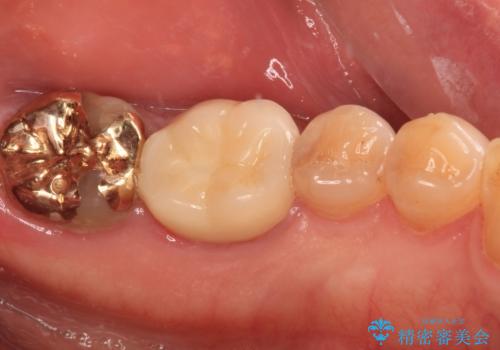

1番奥の歯はゴールドインレー周りがむし歯で欠けており、手前の歯はインレーの下にむし歯がある状態でした。

1番奥は歯肉に覆われている部分が大きいため、欠損部とむし歯の部分をゴールドインレーにて修復し、手前の歯はオールセラミッククラウンにて補綴治療を行うこととしました。